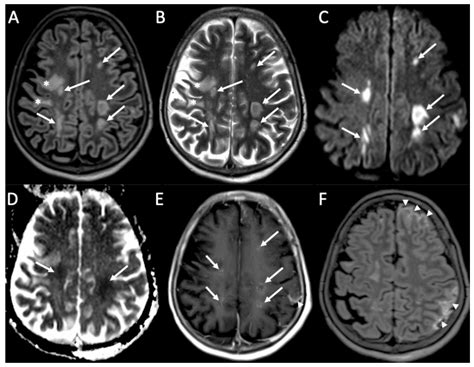

• Imaging tests such as CT scans or MRIs to visualize brain inflammation

• Electroencephalogram (EEG) to detect abnormal brain activity